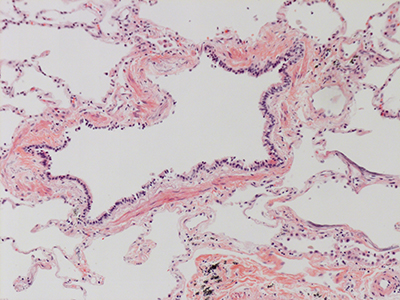

31 Year Old Adult Human Lung DD034L H&E